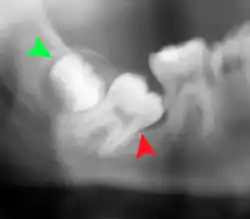

Impacted wisdom teeth are classified by their direction of impaction, their depth compared to the biting surface of adjacent teeth and the amount of the tooth's crown that extends through gum tissue or bone. Impacted wisdom teeth can also be classified by the presence or absence of symptoms and disease. Screening for the presence of wisdom teeth often begins in late adolescence when a partially developed tooth may become impacted. Screening commonly includes a clinical examination as well as x-rays such as panoramic radiographs.

The diagnosis of impaction can be made clinically if enough of the wisdom tooth is visible to determine its angulation, depth, and if the patient is old enough that further eruption or uprighting is unlikely. Wisdom teeth continue to move to the age of 25 years old due to eruption, and then continue some later movement owing to periodontal disease.[18]

If the tooth cannot be assessed with clinical exam alone, the diagnosis is made using either a panoramic radiograph or cone-beam CT. Where unerupted wisdom teeth still have eruption potential several predictors are used to determine the chance of the teeth becoming impacted. The ratio of space between the tooth crown length and the amount of space available, the angle of the teeth compared to the other teeth are the two most commonly used predictors, with the space ratio being the most accurate. Despite the capacity for movement into early adulthood, the likelihood that the tooth will become impacted can be predicted when the ratio of space available to the length of the crown of the tooth is under 1.[5]: 141